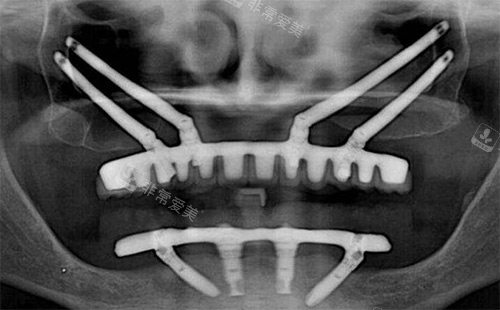

穿颧穿翼种植拍片

技术成熟,适应范围广:传统种植需要足够牙槽骨,穿颧穿翼则直接将植体植入颧骨或翼板,即使骨量不足也能稳定固位,适合半口/全口缺失、牙槽骨吸收重度的患者。

创伤小,修复快:借助3D导航更准一些定位,手术切口小,出血量少,术后肿胀轻,一般3-5天就能消肿,比传统植骨手术修复时间缩短一半。

结果稳定,使用时间长:颧骨和翼板骨密度高,植体与骨结合牢固,临床数据显示,穿颧穿翼种植10年成功几率达95%以上,适合希望长期使用的患者。